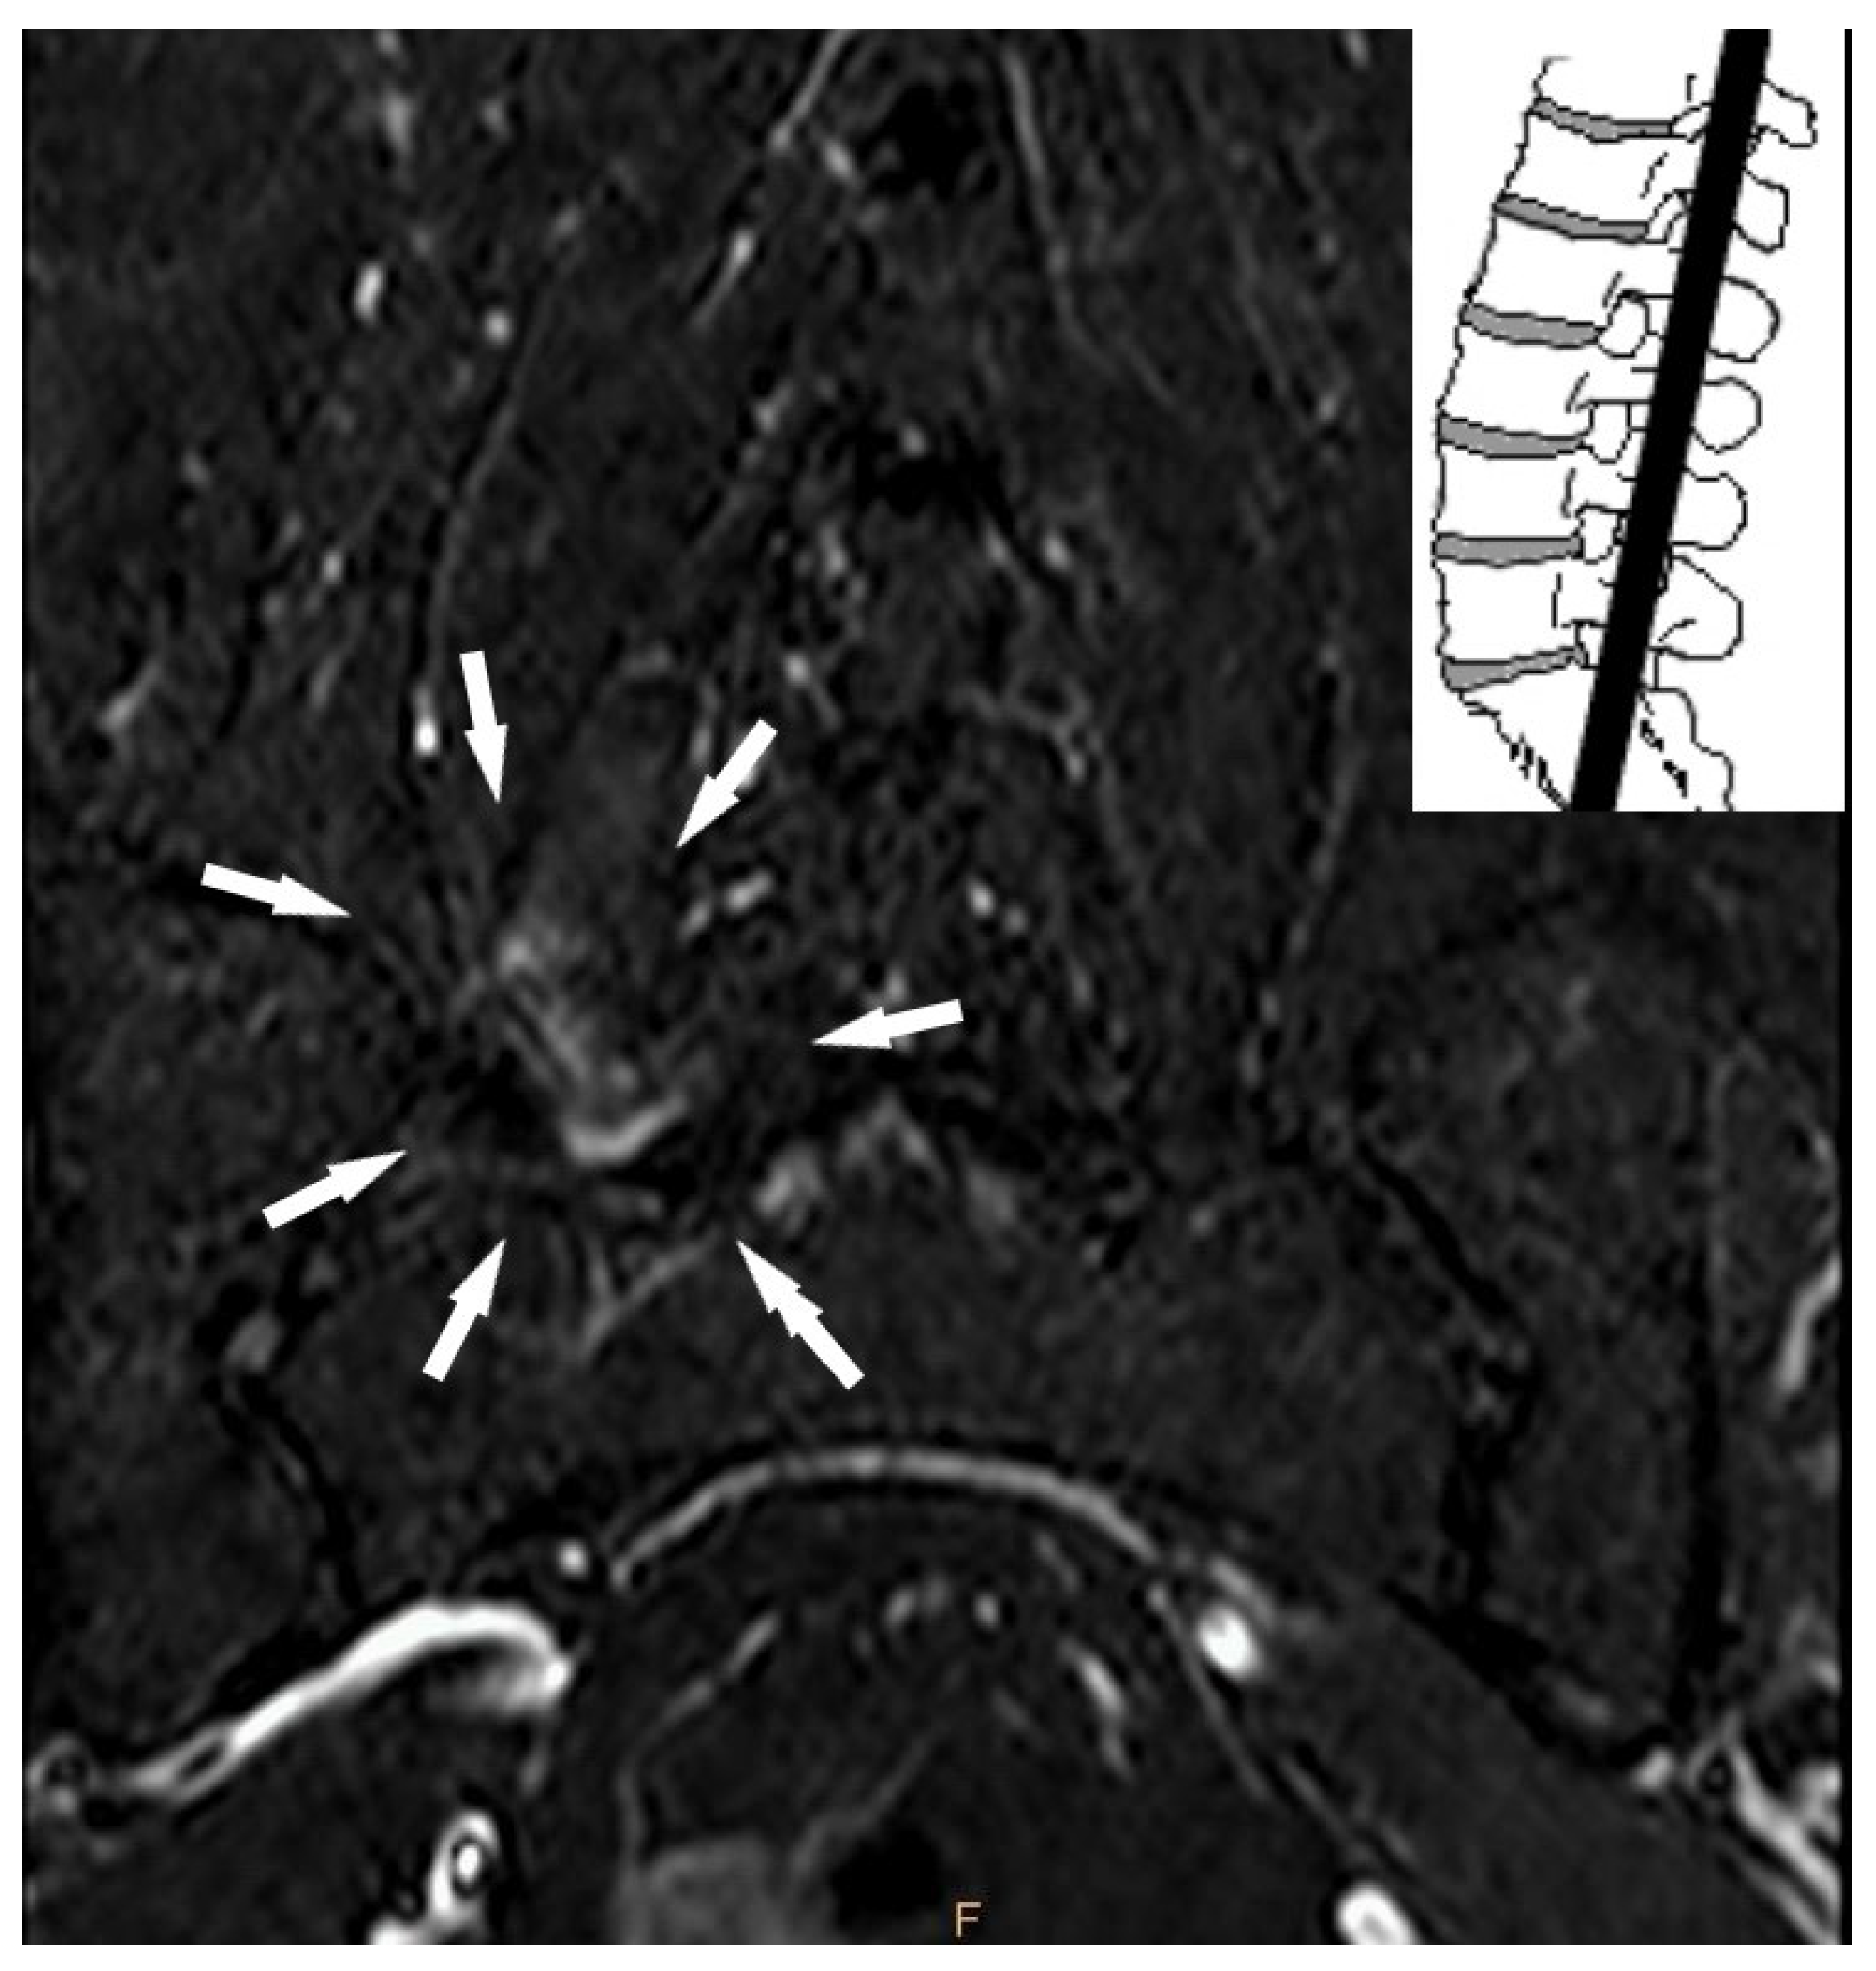

- Lumbar facet joint edema;

- Facet effusion with axial loading.

| Lumbar facet joint edema | Absent | 53 | 58.9 |

| Present | 37 | 41.1 | |

| Facet effusion thickness, mm | 0 | 72 | 80.0 |

| >0 | 18 | 20.0 |

| Facet effusion thickness, mm > 0 | 1.522 | 0.721 | 0.035 | 4.580 | 1.114 | 18.830 |

| Lumbar facet joint edema (present) | 1.858 | 0.617 | 0.003 | 6.412 | 1.913 | 21.492 |